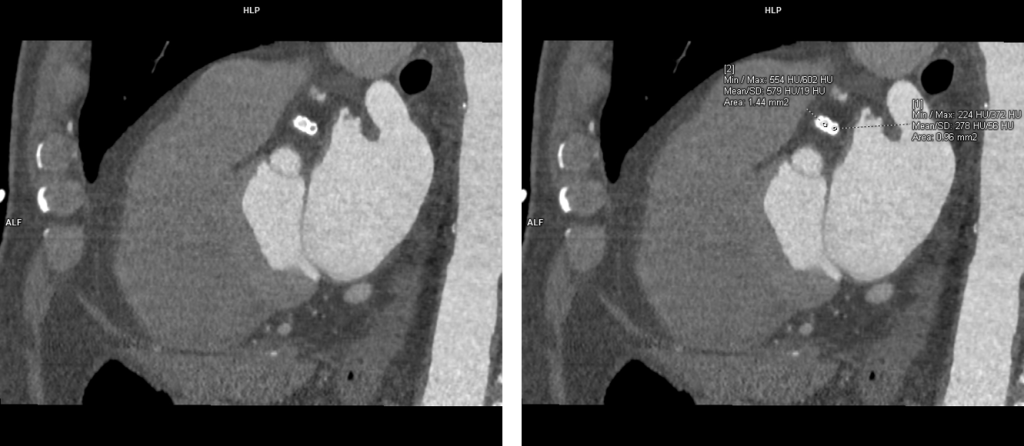

Stenturile situate proximal la nivelul arterelor coronare au lumen suficient de mare ca să poate fi vizualizat prin CT, însă cu cat lumenul e mai mic şi / sau cantitatea de metal din peretele stentului este mai mare, lumenul stentului e mai greu de vizualizat. Examinarea CT NU poate vizualiza sensul de curgere al sângelui, de aceea faptul că după stent se pune în evidenţă densitate intraluminală egală cu cea din vasele de vecinătate, nu înseamnă ca stentul este permeabil; contrastul poate că a ajuns aici prin colaterale ca flux retrograd.

Stenturile coronariene proximale sunt în general corect evaluate prin examinare angioCT cardiacă cu sincronizare ECG pe aparate cu cel putin 64 de detectori. Prin examinare CT nu se poate vizualiza sensul de curgere a sângelui.